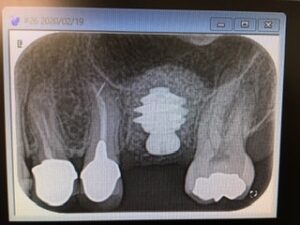

本日は分院の浅草橋にて朝イチから左上6番のインプラントオペ 骨質が柔らかく、抜歯窩の面積が広い為に、最大径のワイドインプラント埋入 径8ミリ、長さ7ミリ、表面積239㎟ ディープスレッドの食い込みに助けられましたね! 固定もとれて、マアマアの値で良かったですね! お疲れ様でした 須田寛昌医師談

本日は分院の浅草橋にて朝イチから左上6番のインプラントオペ 骨質が柔らかく、抜歯窩の面積が広い為に、最大径のワイドインプラント埋入 径8ミリ、長さ7ミリ、表面積239㎟ ディープスレッドの食い込みに助けられましたね!

固定もとれて、マアマアの値で良かったですね! お疲れ様でした 須田寛昌医師談